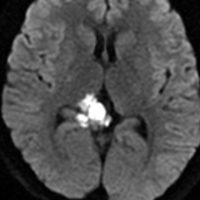

10代で発見された四丘体槽の類表皮のう胞です。左の画像,拡散強調像 DWIで真っ白に見えるので診断できます。真ん中は発見された時のもの,右側の画像は7年後です。ゆっくり増大してきたので,開頭手術(経テント法)で完全摘出しました。周囲の血管や神経に癒着するのでそれほど簡単な手術ではありません。